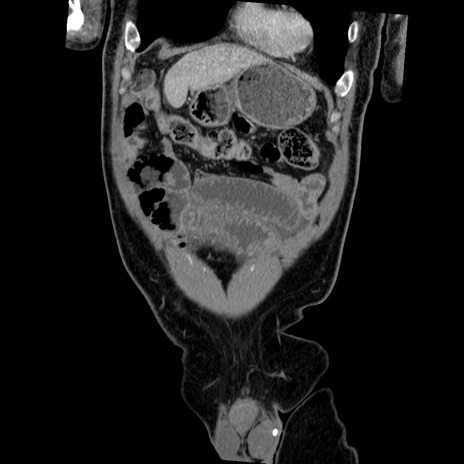

症例22(冠状断像)

【症例】50歳代男性

【主訴】腹痛

【現病歴】AVMからの被殻出血のため回復期リハ病棟入院中。 本日午後3時頃急に下腹部痛が出現した。

【既往歴】AVM、被殻出血、虫垂炎、高血圧

【身体所見】意識晴明、左半身不全麻痺、会話の理解は良好、36.5°C、腹部:膨隆、全体に板状硬、下腹部正中に圧痛点あり、反跳痛-、筋性防御不明、右下腹部にope scar

【データ】WBC 9400、CRP 0.06